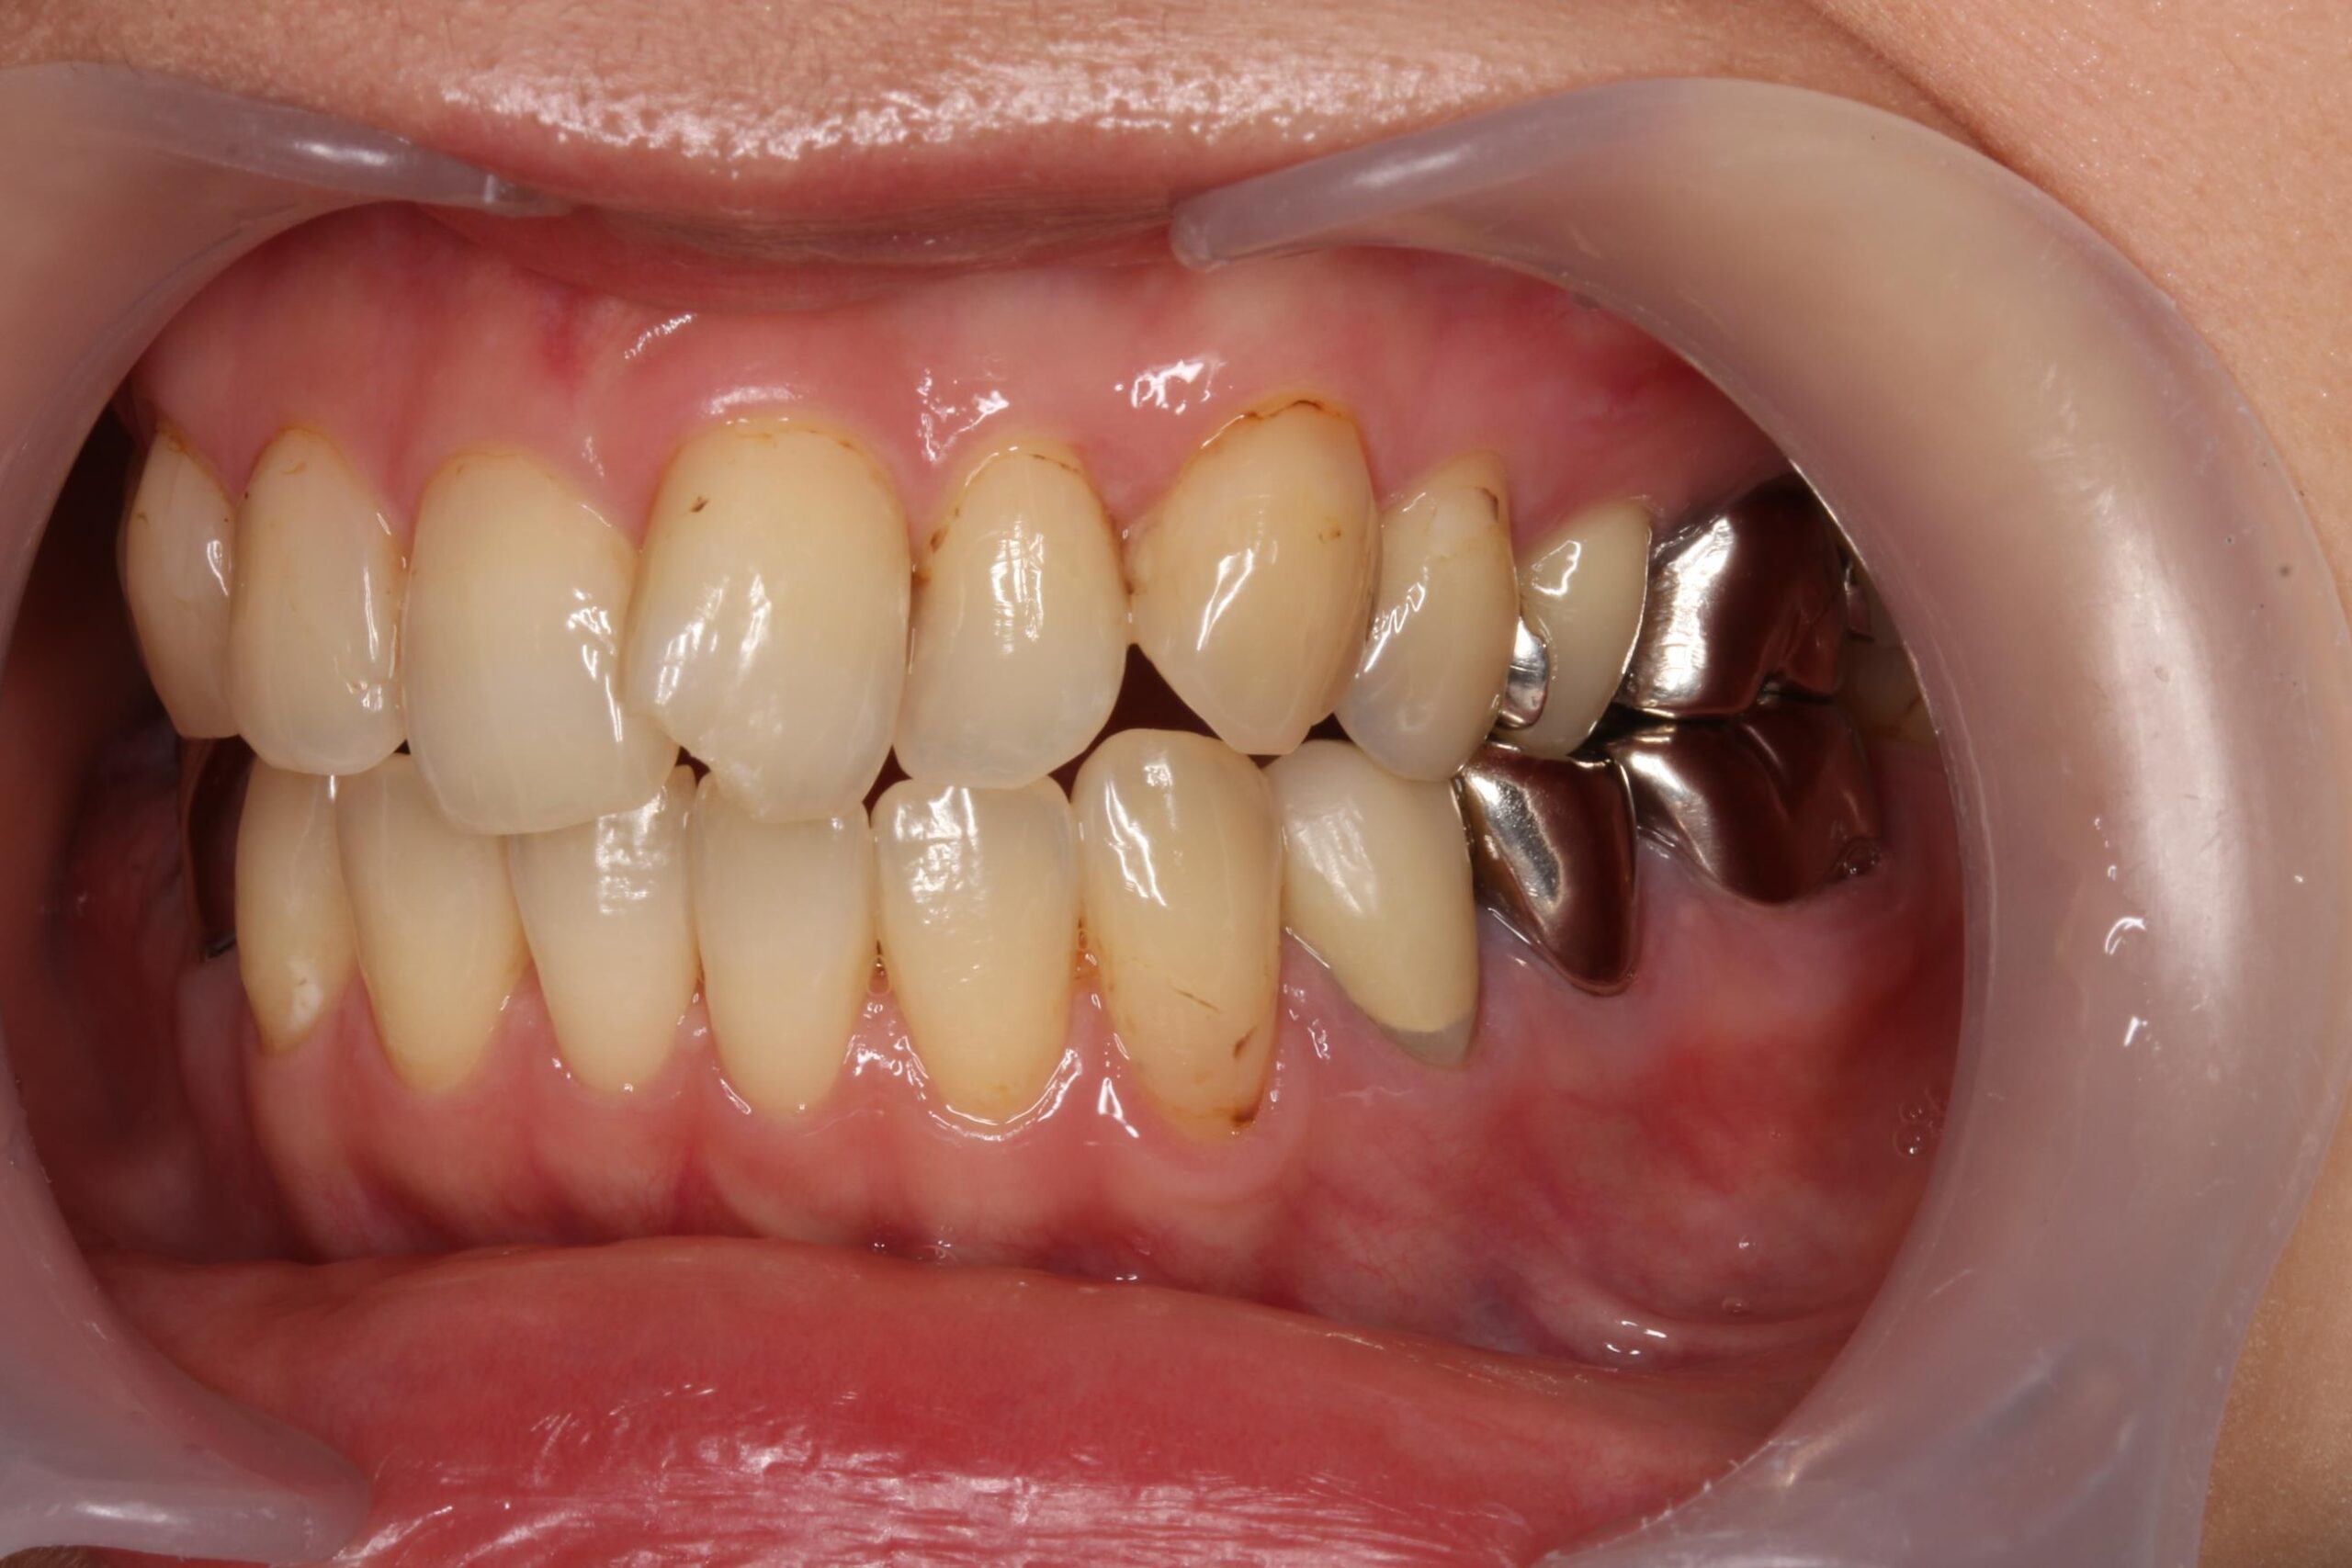

症例02

70代 男性 咬み合わせが強く多くの歯がすぐに壊れる

| 主訴 | 咬み合わせが強く、治療をしてもつくった歯がすぐに壊れる。 他院ではインプラントをいれることも難しいため、断られた。 |

|---|---|

| 年代・性別 | 70代 男性 |

| 治療部位 | 下顎両側 5,6 上顎右側 4 6のインプラントブリッジ ※全顎的に、臨床的歯冠長延長術(クラウンレングスニング)を行い、セラミッククラウンの強度を増しています。 |

| 治療費用 | インプラント 440,000円×6本 |

| 手術回数 | 下顎1回 上顎1回 |

| 治療期間 | 下顎6ヶ月 上顎6ヶ月 |

| 手術時間 | 下顎90分 上顎60分 |

| 治療回数 | 下顎1回 上顎1回 |